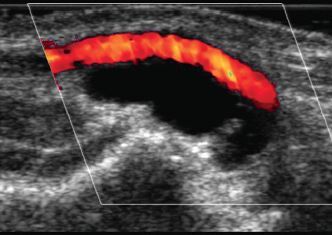

Varicocele

Varicoceles are dilated veins of the pampiniform plexus. They are almost always caused by incompetent valves within the internal spermatic vein. Normal peritesticular veins should be less than 2 or 3 mm in diameter. In my experience, they seldom exceed 2 mm. On color Doppler scanning, venous flow in varicoceles is generally too slow to be detected with the patient at rest. Sometimes, this slow flow is apparent on gray-scale imaging. With a Valsalva maneuver, there is augmented retrograde flow in the varicocele that is readily detectable on color Doppler imaging. This augmented flow usually lasts longer than 1 second.